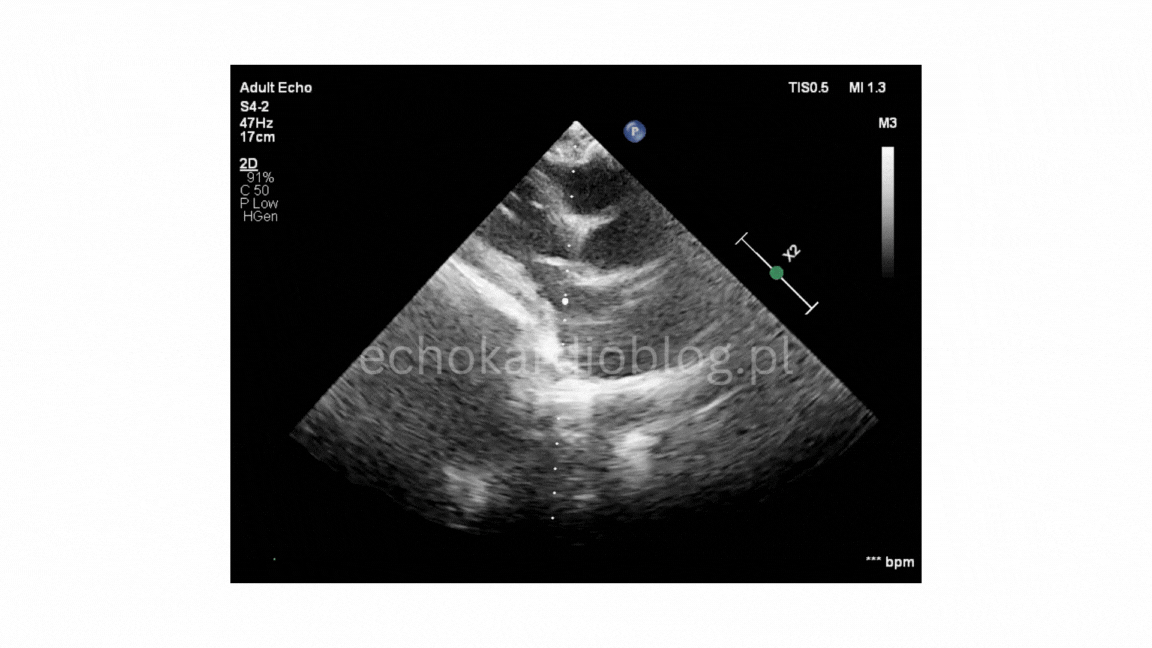

Prezentuję dwa przypadki pseudodyskinezy u pacjentów z marskością wątroby z wodobrzuszem:

przypadek 2, gdzie jest mniej nasilona postać pseudodyskinezy

We present two cases of pseudodyskinesia in patents with liver cirrhosis and ascites:

Case 2- a less pronounced form of the są me phenomenon.